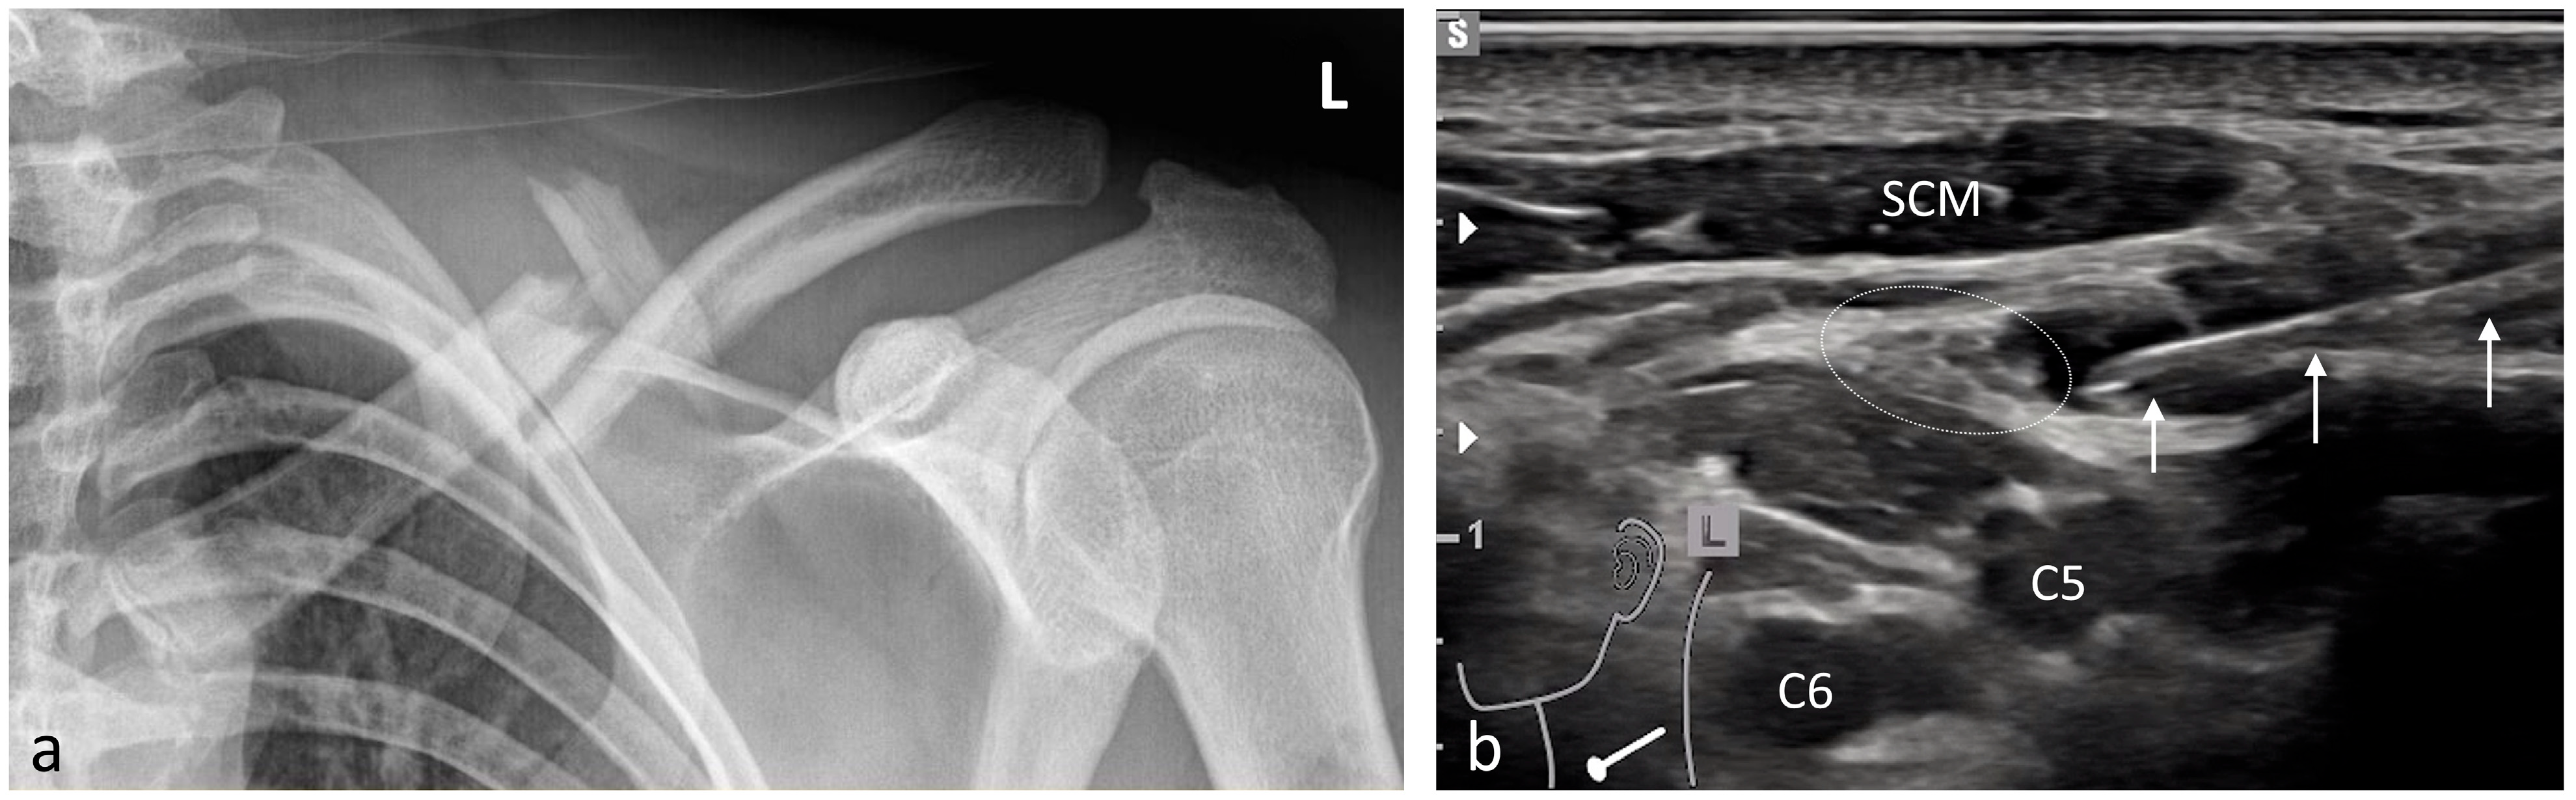

| Scapula | 8 | Brachial plexus block (interscalene)/3–5 |

| Shoulder | 99 | Brachial plexus block (interscalene)/3–5 |

| Shoulder prosthesis | 5 | Brachial plexus block (interscalene)/3–5 |